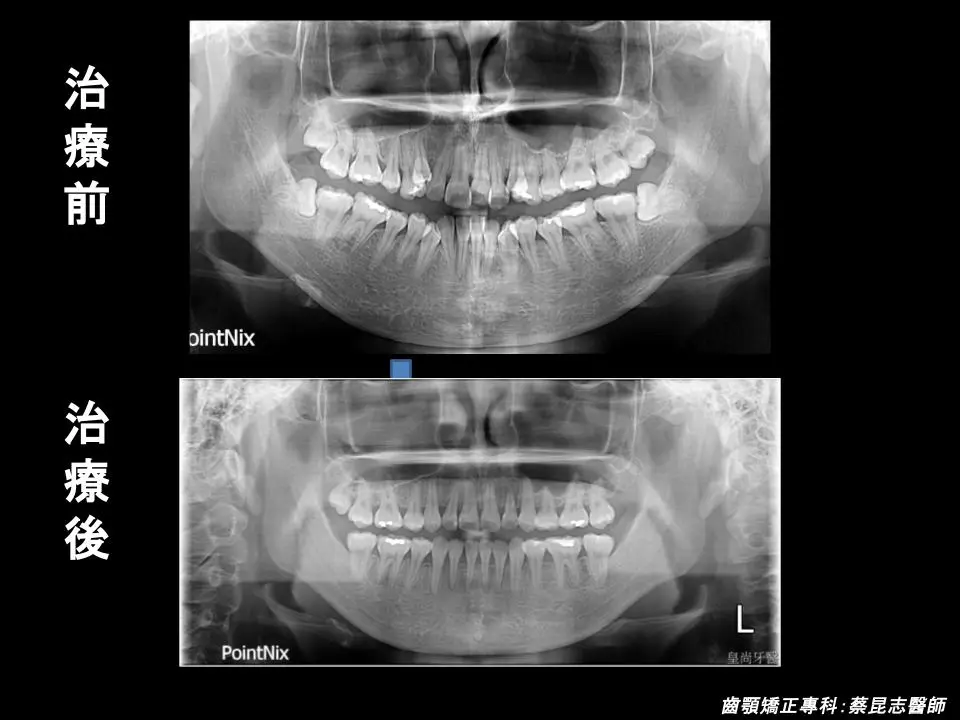

【牙齒矯正】前牙錯咬矯正,告別戽斗重拾自信笑容

前牙錯咬戽斗案例-牙況說明

治療前可以見到因為上下顎前牙嚴重擁擠、上顎高位犬齒,所造成的不美觀笑容。

又因為下顎前牙過於外暴、上下顎前牙咬合與正常咬合相反的錯咬,所造成的側面輪廓下唇的部分過於外凸。

前牙錯咬戽斗案例-結果分享

前牙錯咬戽斗矯正前後臉型變化 前牙錯咬戽斗矯正前後口腔變化 前牙錯咬戽斗矯正前後口腔側面變化 前牙錯咬戽斗矯正前後門牙變化 前牙錯咬戽斗矯正前後嘴型變化 前牙錯咬戽斗矯正前後正面x光變化 前牙錯咬戽斗矯正前後側面x光變化